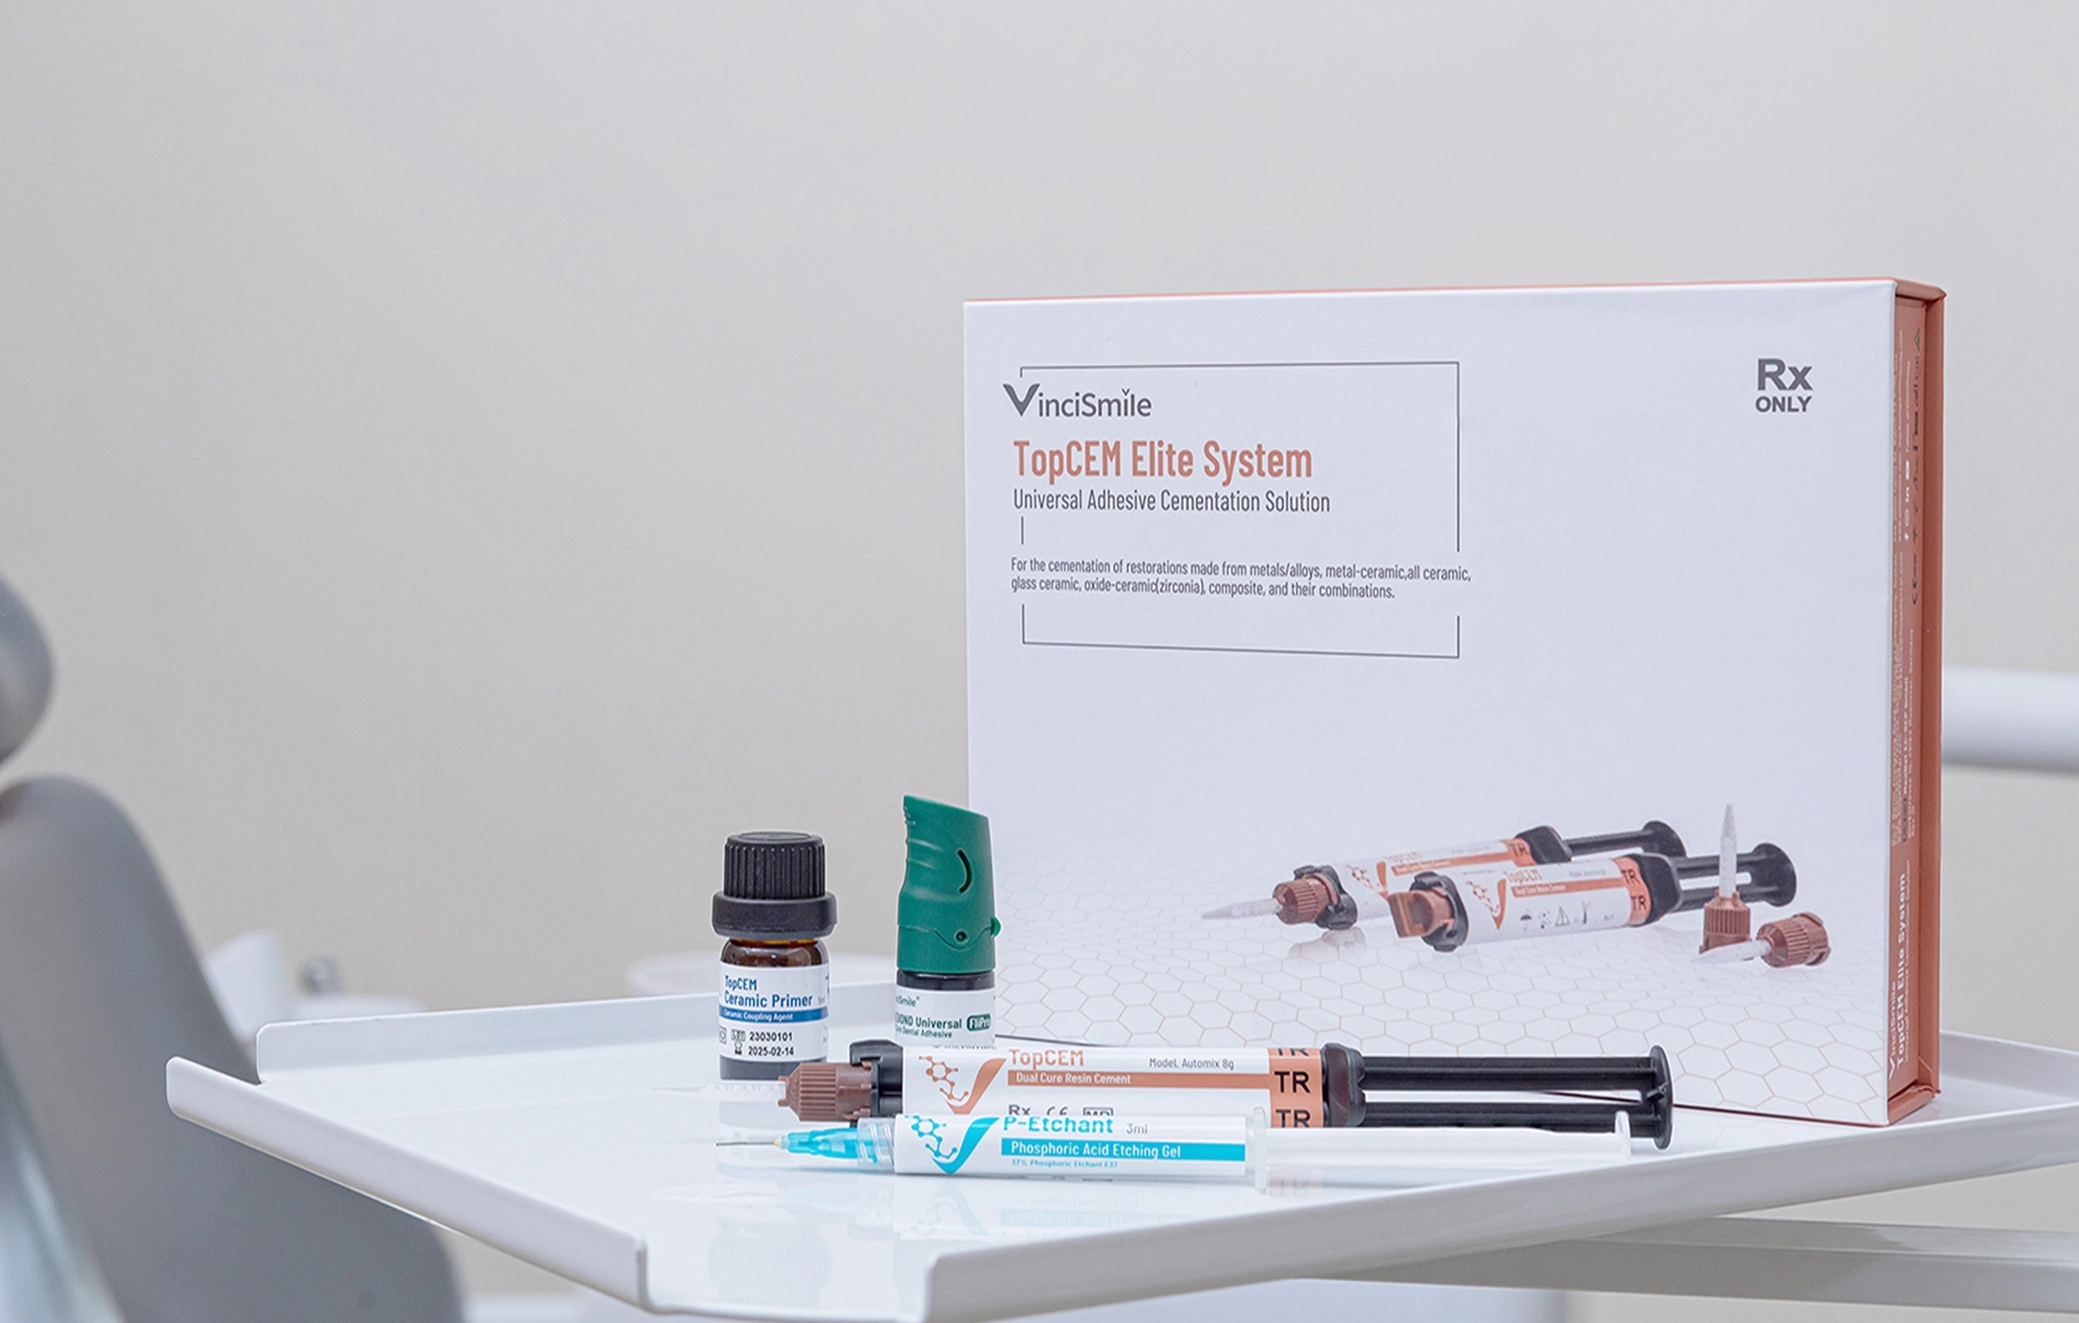

Cementing

Once the printing is complete, it's suggested to use self-curing resin as bonding material for bonding the teeth in the denture bases. According to test, it's time-saving, cheaper and easier to clean.

Learn More About the Products: